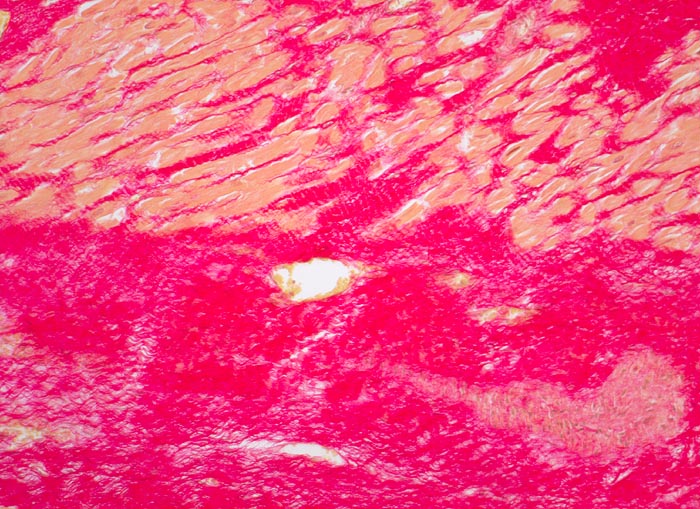

Myokardinfarktnarbe

Abschnitte der Muskulatur ersetzt durch siriusrote, wellige Kollagenfaserbündel (Kollagen Typ I). In den Ausläufern der Narbe perizelluläre Fibrose um das überlebende Myokard. Stellenweise in Narbenfeldern noch weite Kapillaren. Fokal zellreicherer Narbenabschnitt mit Fibroblasten/-zyten.

Schwere stenosierende Sklerose der rechten Koronararterie. 4x5cm grosse Narbe im Bereich der Hinterwand.

Diabetes mellitus. St.n. Hinterwandinfarkt vor 3 Jahren